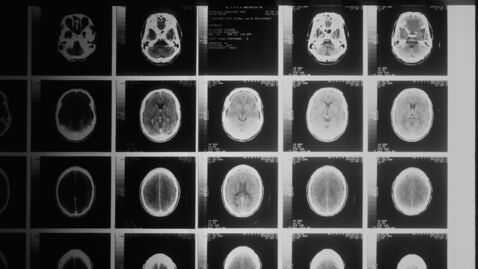

A CT scan was done, which showed that he had intracerebral hemorrhage (ICH), with bleeding in the lower left side of his brain!